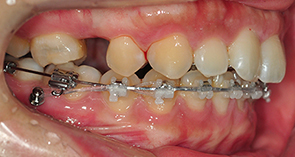

그리고는 고무줄도 새로운것으로 갈고 치아 중심선이 잘 맞는지도 봐주셨어요. 이~ 해서 위아래 치아선이 직선으로 잘 맞는지 봐주셨어요. 고무줄도 상악과 하악 둘다 새로운것으로 갈았어요

킬본장치, 상악에 새로운 고무줄로 갈았는데 아주 팽팽해서 새로운걸 하긴했구나하는 생각이 확들었어요 ㅋㅋ

고무줄을 새로 교체까지 완료후 집으로 돌아왔는데 집에가는길에 뭔가 툭! 하는 느낌이 드는거에요 그래서 거울을 들여다 봤더니 고무줄이 뭔가 끊어진 것으로 보이더라구요

다시 치과에 내원하였더니 원장선생님이 '어?' 그러시면서 다시 봐주셨어요 ㅋㅋ 저는 집에가는길이 고무줄이 끊어진것 같다고 말씀드렸는데 고무줄이 두줄로 된 부분중에 한줄이 끊어진것이었어요

고무줄을 교체해주시면서 의사선생님이 설명을 해주셨는데 두줄인것에서 하나만 끊어졌을때는 굳이 내원하지 않아도 된다고 하시더라구요 하나만 연결되어있어도 크게 문제 되지 않는다고